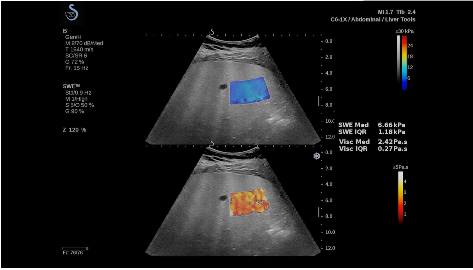

法國(guó)聲科影像(SuperSonic Imagine,SSI. Euroniex:FR0010526814)近日發(fā)表公告,宣布其研發(fā)的新一代“極速”超聲成像平臺(tái)(UltraFast Imaging),首次實(shí)現(xiàn)了肝臟的多項(xiàng)超聲定量評(píng)估新指標(biāo)同步檢測(cè),包括:Att PLUS,SSp PLUS和Vi PLUS等,基本涵蓋肝臟相關(guān)病理變化指征的如纖維化、脂肪變、炎癥等。據(jù)悉,此多項(xiàng)新技術(shù)新將搭載于新Aixplorer系列E超系統(tǒng)。